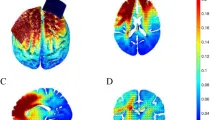

ТЭС проводилась с использованием стимулятора Neuroconn через два смоченных в солевом растворе электрода размером 5 × 5 см. Референтный электрод располагался на правой орбитофронтальной области, а целевой электрод — над точкой F3 (система EEG 10–20). Четыре группы активной стимуляции включали различные комбинации полярности и интенсивности: анодная 1,0 мА, катодная 1,0 мА, катодная 1,5 мА и катодная 2,0 мА. Общая продолжительность стимуляции составляла 20 минут, включая 30-секундный период нарастания и спада. Участники в группе плацебо также проходили 30-секундный период нарастания, но получали только 15 секунд активной стимуляции, после чего стимуляция снижалась в течение еще 30 секунд (общая продолжительность стимуляции — 1 минута 15 секунд). Во время стимуляции участников просили сидеть спокойно с открытыми глазами.

ТЭС

Для обозначения расположения электродов при описании полярности стимуляции используются знаки '+' для анодной и '-' для катодной. Целевые области обозначаются как PFC (префронтальная кора) и IPL (нижняя теменная доля). Использовались две полярности: 1 мА и 2 мА. Было пять экспериментальных групп: (1) анод/катод над левой PFC/правой IPL при 1 мА (1 мА +PFC/−IPL); (2) анод/катод над левой PFC/правой IPL при 2 мА (2 мА +PFC/−IPL); (3) катод/анод над левой PFC/правой IPL при 1 мА (1 мА +IPL/−PFC); (4) катод/анод над левой PFC/правой IPL при 2 мА (2 мА +IPL/−PFC); и (5) плацебо-стимуляция с чередующимся расположением электродов и дозировками активных групп стимуляции.